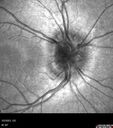

8 year old boy with headache and nausea. He had a negative MRI. Images show hyper FAF from drusen and no leakage on FA. No spinal tap was done. VA was 20/40 both eyes.

Disc drusen 8 year old boy - fluorescein shows no leakage175 views8 year old boy with headache and nausea. He had a negative MRI. Images show hyper FAF from drusen and no leakage on FA. No spinal tap was done. VA was 20/40 both eyes.00000